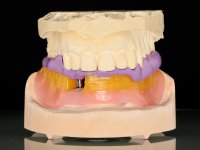

After clinical and radiological evaluation several rehabilitation plans were discussed with the patient. It was decided to extract the remaining lower teeth and do an overdenture retained by two dental implants with the locator attachement system to achieve a better retention and stabilization of the lower denture.

Two dental implants were planned in the CBCT scan, in the area of the inferior canines. The dental extractions were performed and, simultaneously, the alveolar crest was flattened and the implants were placed. Three issues were considered while implant placement: parallelism of the axis, same height of the implant’s neck, and same position in the coronal plan. This 3D insertion is essential to have a good retention of the overdenture in the future. Patient’s removable denture was fixed in the dental lab, to include the extracted teeth, and a soft-tissue relining was done over the healing abutments. After the osseo-integration period, a first impression was done with an open-tray and a doble-mix technique. This dental impression allowed the production of screwed wax-rims and an individual tray for a functional impression. A second impression, final, was done with an individual tray with a monophasic silicone. The occlusal wax-rims were correct in the mouth according to the full denture guidelines. Special care was taken with the occlusal vertical dimension and the support in the soft-tissues. A silicone bite registration material was used to better defined the intermaxillary relations. Teeth set-up was done in the dental lab with the selected tooth color. Due to the fact that the base was screwed to the dental implants, the teeth set-up was functionally evaluated in the mouth. Another silicone bite registration material was used to allow final occlusal adjustments. Finally, the locators were screwed and the retention nylons were selected according to the patient needs.